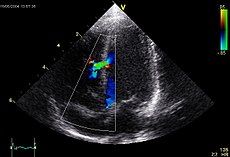

پژواکنگاری قلب یا اکوکاردیوگرافی (Echocardiography) که به آن "سونوگرافی قلب" یا "اکوی قلب" هم گفته میشود روشی غیر تهاجمی است که با استفاده از امواج صوتی، ساختمان داخلی قلب به تصویر کشیده میشود و در حقیقت به عنوان استاندارد تشخیص بیماریهای قلبی تلقی میشود.